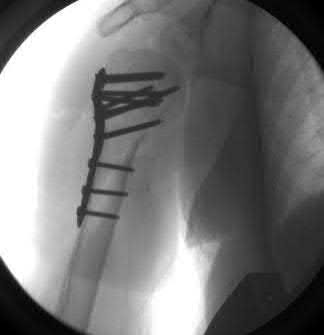

A 68-year-old osteoporotic female sustains a proximal humerus fracture. The AP radiograph is shown. According to the Hertel criteria, which of the following radiographic features is the most reliable predictor of humeral head ischemia?

Options:

- Anatomical neck fracture pattern

- Greater tuberosity displacement > 1 cm

- Metaphyseal head extension (calcar segment) less than 8 mm

- Varus angulation greater than 20 degrees

- Disruption of the medial periosteal hinge > 2 mm

Correct Answer: Metaphyseal head extension (calcar segment) less than 8 mm

Explanation:

Hertel et al. described radiographic criteria predictive of humeral head ischemia. The most reliable predictors include a metaphyseal head extension (calcar segment) of less than 8 mm, disruption of the medial hinge (>2 mm), and an anatomic neck fracture. Among the choices, the calcar segment length < 8 mm represents a highly predictive sign that the primary blood supply (the ascending branch of the anterior humeral circumflex artery and intraosseous vessels) has been severely compromised.